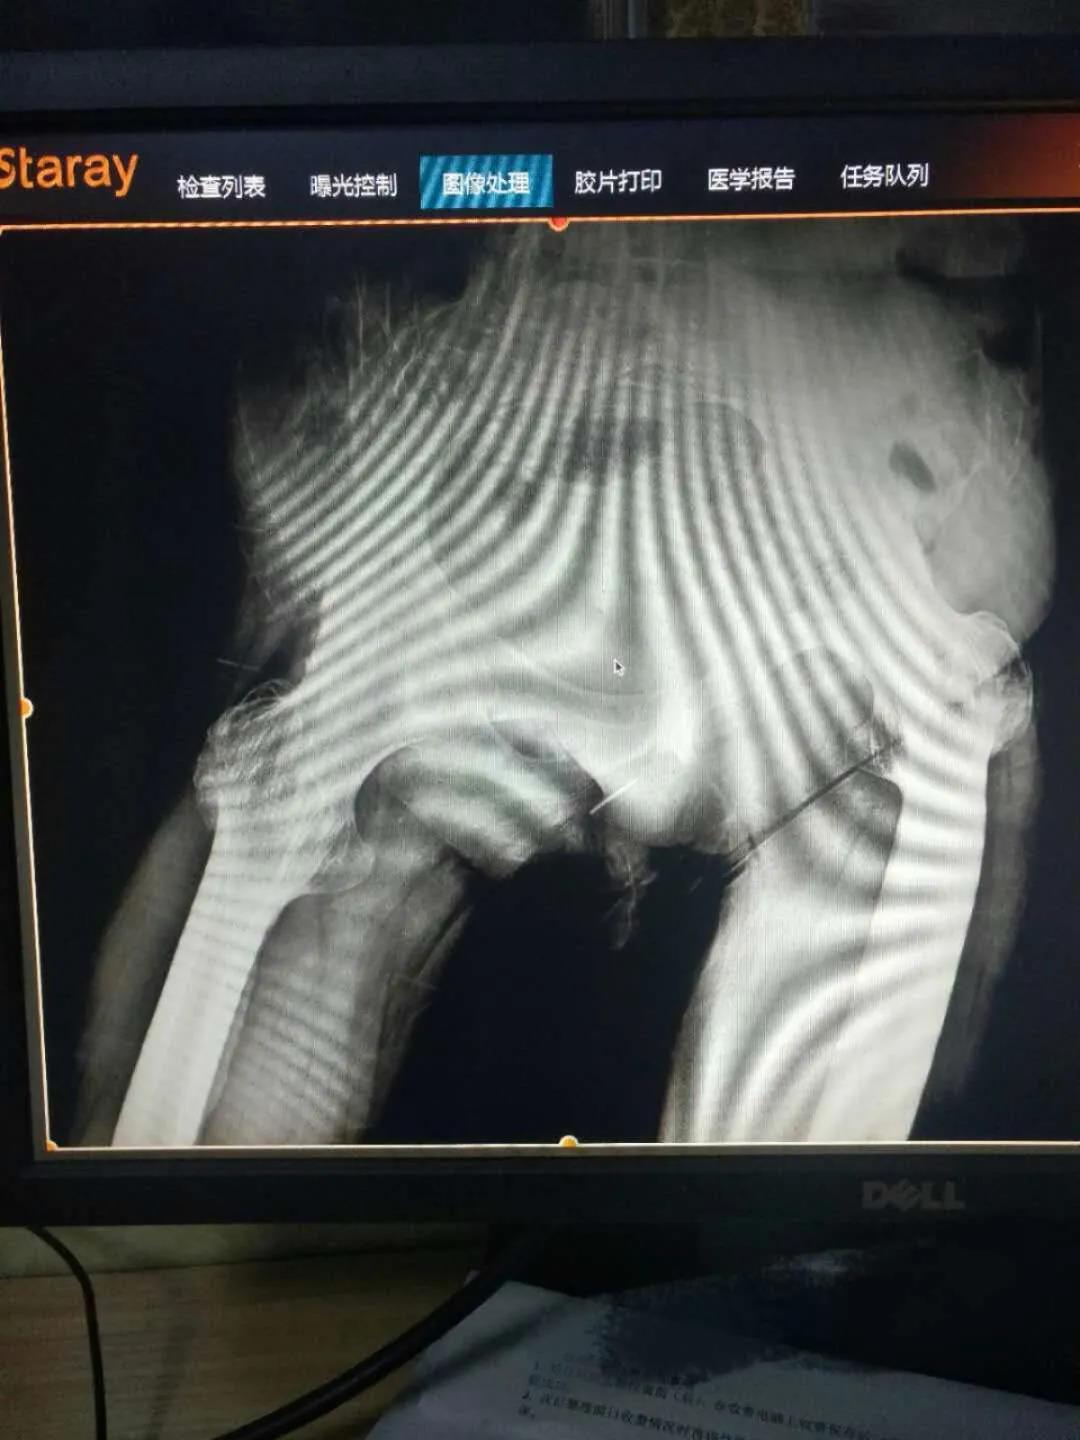

保髖治療

成人股骨頭無菌性壞死為成人常見髖關節(jié)疾病,導致髖關節(jié)周圍疼痛,最終導致患者行走困難,骨二科根據患者患者股骨頭壞死的ARCO分期,早期采用髖關節(jié)鏡加自體打壓植骨并PRP治療,能夠使股骨頭壞死區(qū)域血管再通,恢復髖關節(jié)的功能,避免最終的髖關節(jié)置換。

髖關節(jié)置換治療

髖關節(jié)疾病終末期股骨頭塌陷或關節(jié)破壞較重,只能采用髖關節(jié)置換、治療,骨二科采用微創(chuàng)Super-path入路和DAA入路進行髖關節(jié)置換,患者術后當天即可下床活動,術后無痛管理,加速患者術后康復及早日重返社會。

全髖關節(jié)置換